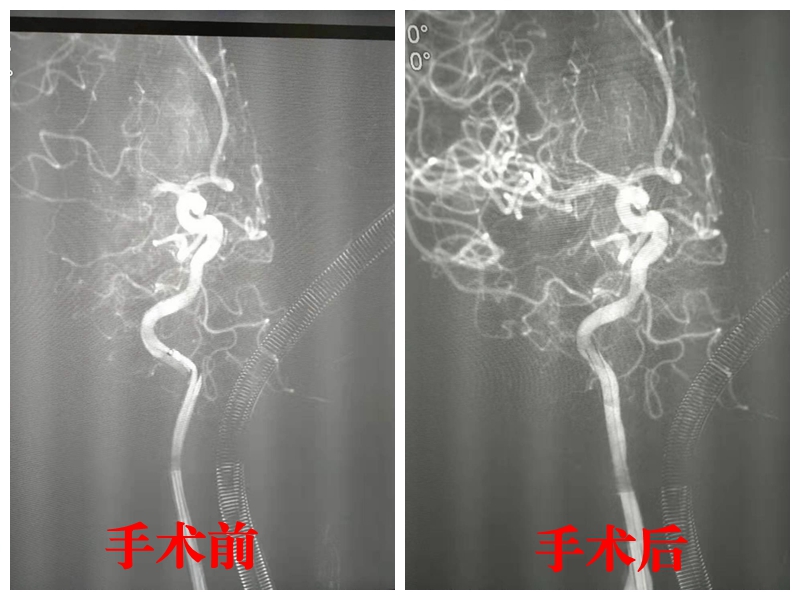

19:40 引导管置于颈内动脉

19:48 行脑血管造影,明确右侧大脑中动脉起始段完全闭塞

19:54 取出血栓

19:59 造影证实闭塞动脉开通

分秒必争、一气呵成,神经外科主任曾怀文带领团队仅用19分钟,成功为李阿婆开通脑血管通路。